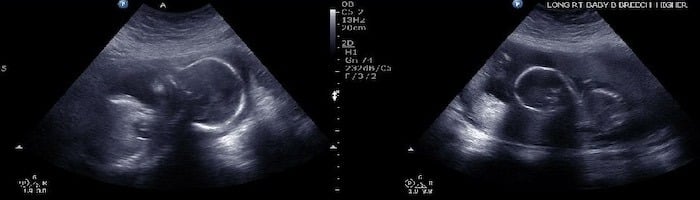

Ultrasound Photos at 25 Weeks Pregnant With Twins